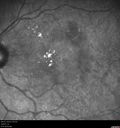

82 year old woman She was in for her yearly checkup and a problem was noted. She does not notice a vision issue. Her mother had AMD but she has no significant other family retina problems. VA OD: Dcc20/25 VA OS: Dcc20/25 The right eye has an inactive subfoveal net only visible on ICG and the left eye has the same in addition to a probable polypoidal choroidal vasculopathy lesion adjacent to the nerve with perifoveal exudate. She was not treated this visit. She has been followed for 6 years. The left eye got better without treatment. The right eye was never treated. At age 88, her vision is 20/25 in both eyes.

Asymptomatic wet AMD - Subfoveal CNM both eyes464 views82 year old woman - 20/25 OU. Images show occult subfoveal CNVM both eyes best seen on late ICG. The left eye also has probable polypoidal choroidal vasculopathy. No treatment was recommended on the first visit - follow-up at 1 month.00000